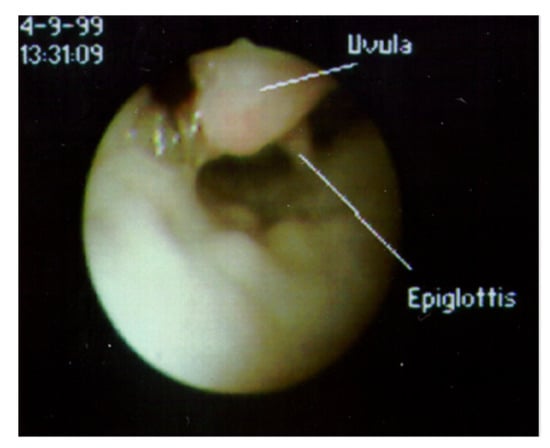

Abnormalities of pharyngeal structures can cause a chronic cough. Tonsils have been associated with a persistent cough when they impinge upon the epiglottis (Figure 4) [13]. The uvula also has been reported to cause a cough when of sufficient length or positioned in such a way that it comes in contact with the epiglottis (Figure 5) [14]. A nocturnal cough is common with both of these causes of cough. When a chronic cough is not associated with any apparent lung disease and does not fit the pattern of a habit cough, flexible bronchoscopy through the nose permits visualization of the upper airway prior to progression to the lower airway. While the tonsils or uvula are not ordinarily a cause of coughing, visualizing their atypical contact with the epiglottis is sufficient to suspect that those observations are the cause of chronic coughing in these children. Treatment includes tonsillectomy or uvulectomy to eliminate the stimulation on the epiglottis. Postoperative cessation of coughing supports this diagnosis.

Figure 5. View of supraglottic area through a flexible fiberoptic bronchoscope inserted through the nose, with the patient supine. The uvula, which cannot normally be observed when the epiglottis is visualized, is lying in contact with the epiglottis.